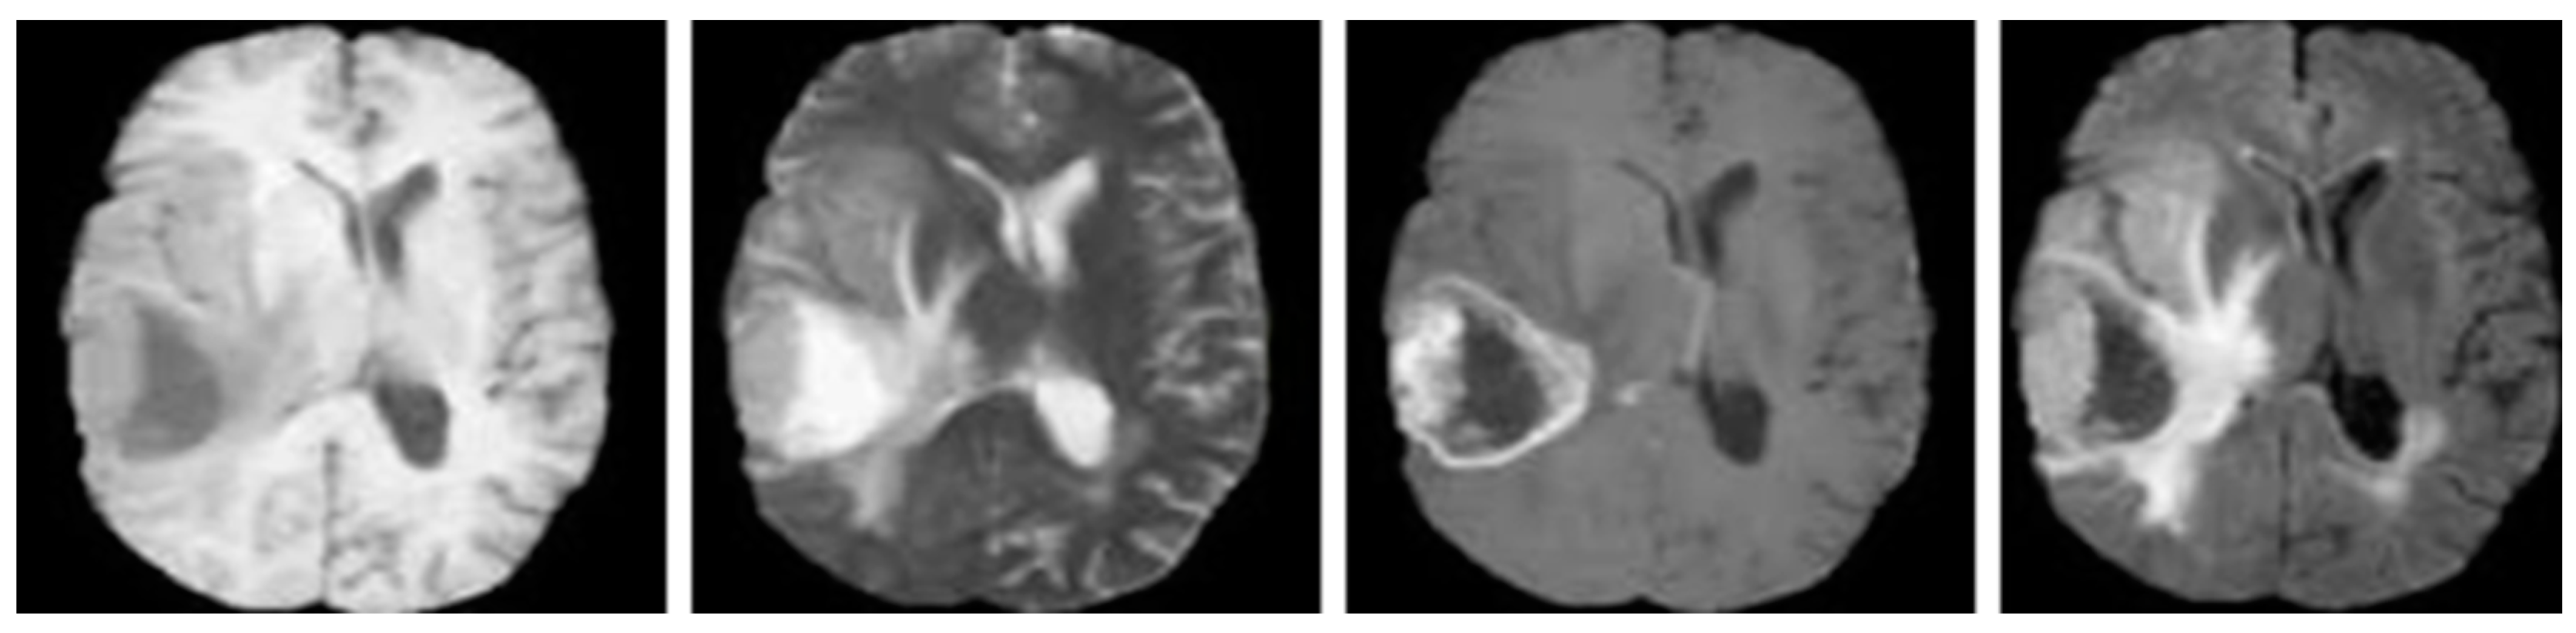

The data are collected from the MRIs of benchmark datasets: BraTS 2019 (https://www.kaggle.com/datasets/aryashah2k/brain-tumor-segmentation-brats-2019, accessed on 1 June 2024), BraTS 2020 (https://www.kaggle.com/datasets/awsaf49/brats20-dataset-training-validation, accessed on 1 June 2024), and BraTS 2021 (https://www.kaggle.com/datasets/dschettler8845/brats-2021-task1/code, accessed on 1 June 2024), which consists of the same dataset, but with different training, testing, and validation sets. These datasets consist of 3D scans of MRI with precise types of brain tumor and the same modalities, such as T1, T1-weighted, T2-weighted, T1ce and FLAIR. The BraTS 2021 consists of 1251 training set, 570 testing set and 219 validation sets. The sample MRI scans of BraTS 2021 is depicted in Figure 2.

Figure 2.

Example MRI brain scans of BraTS 2021 database [34].